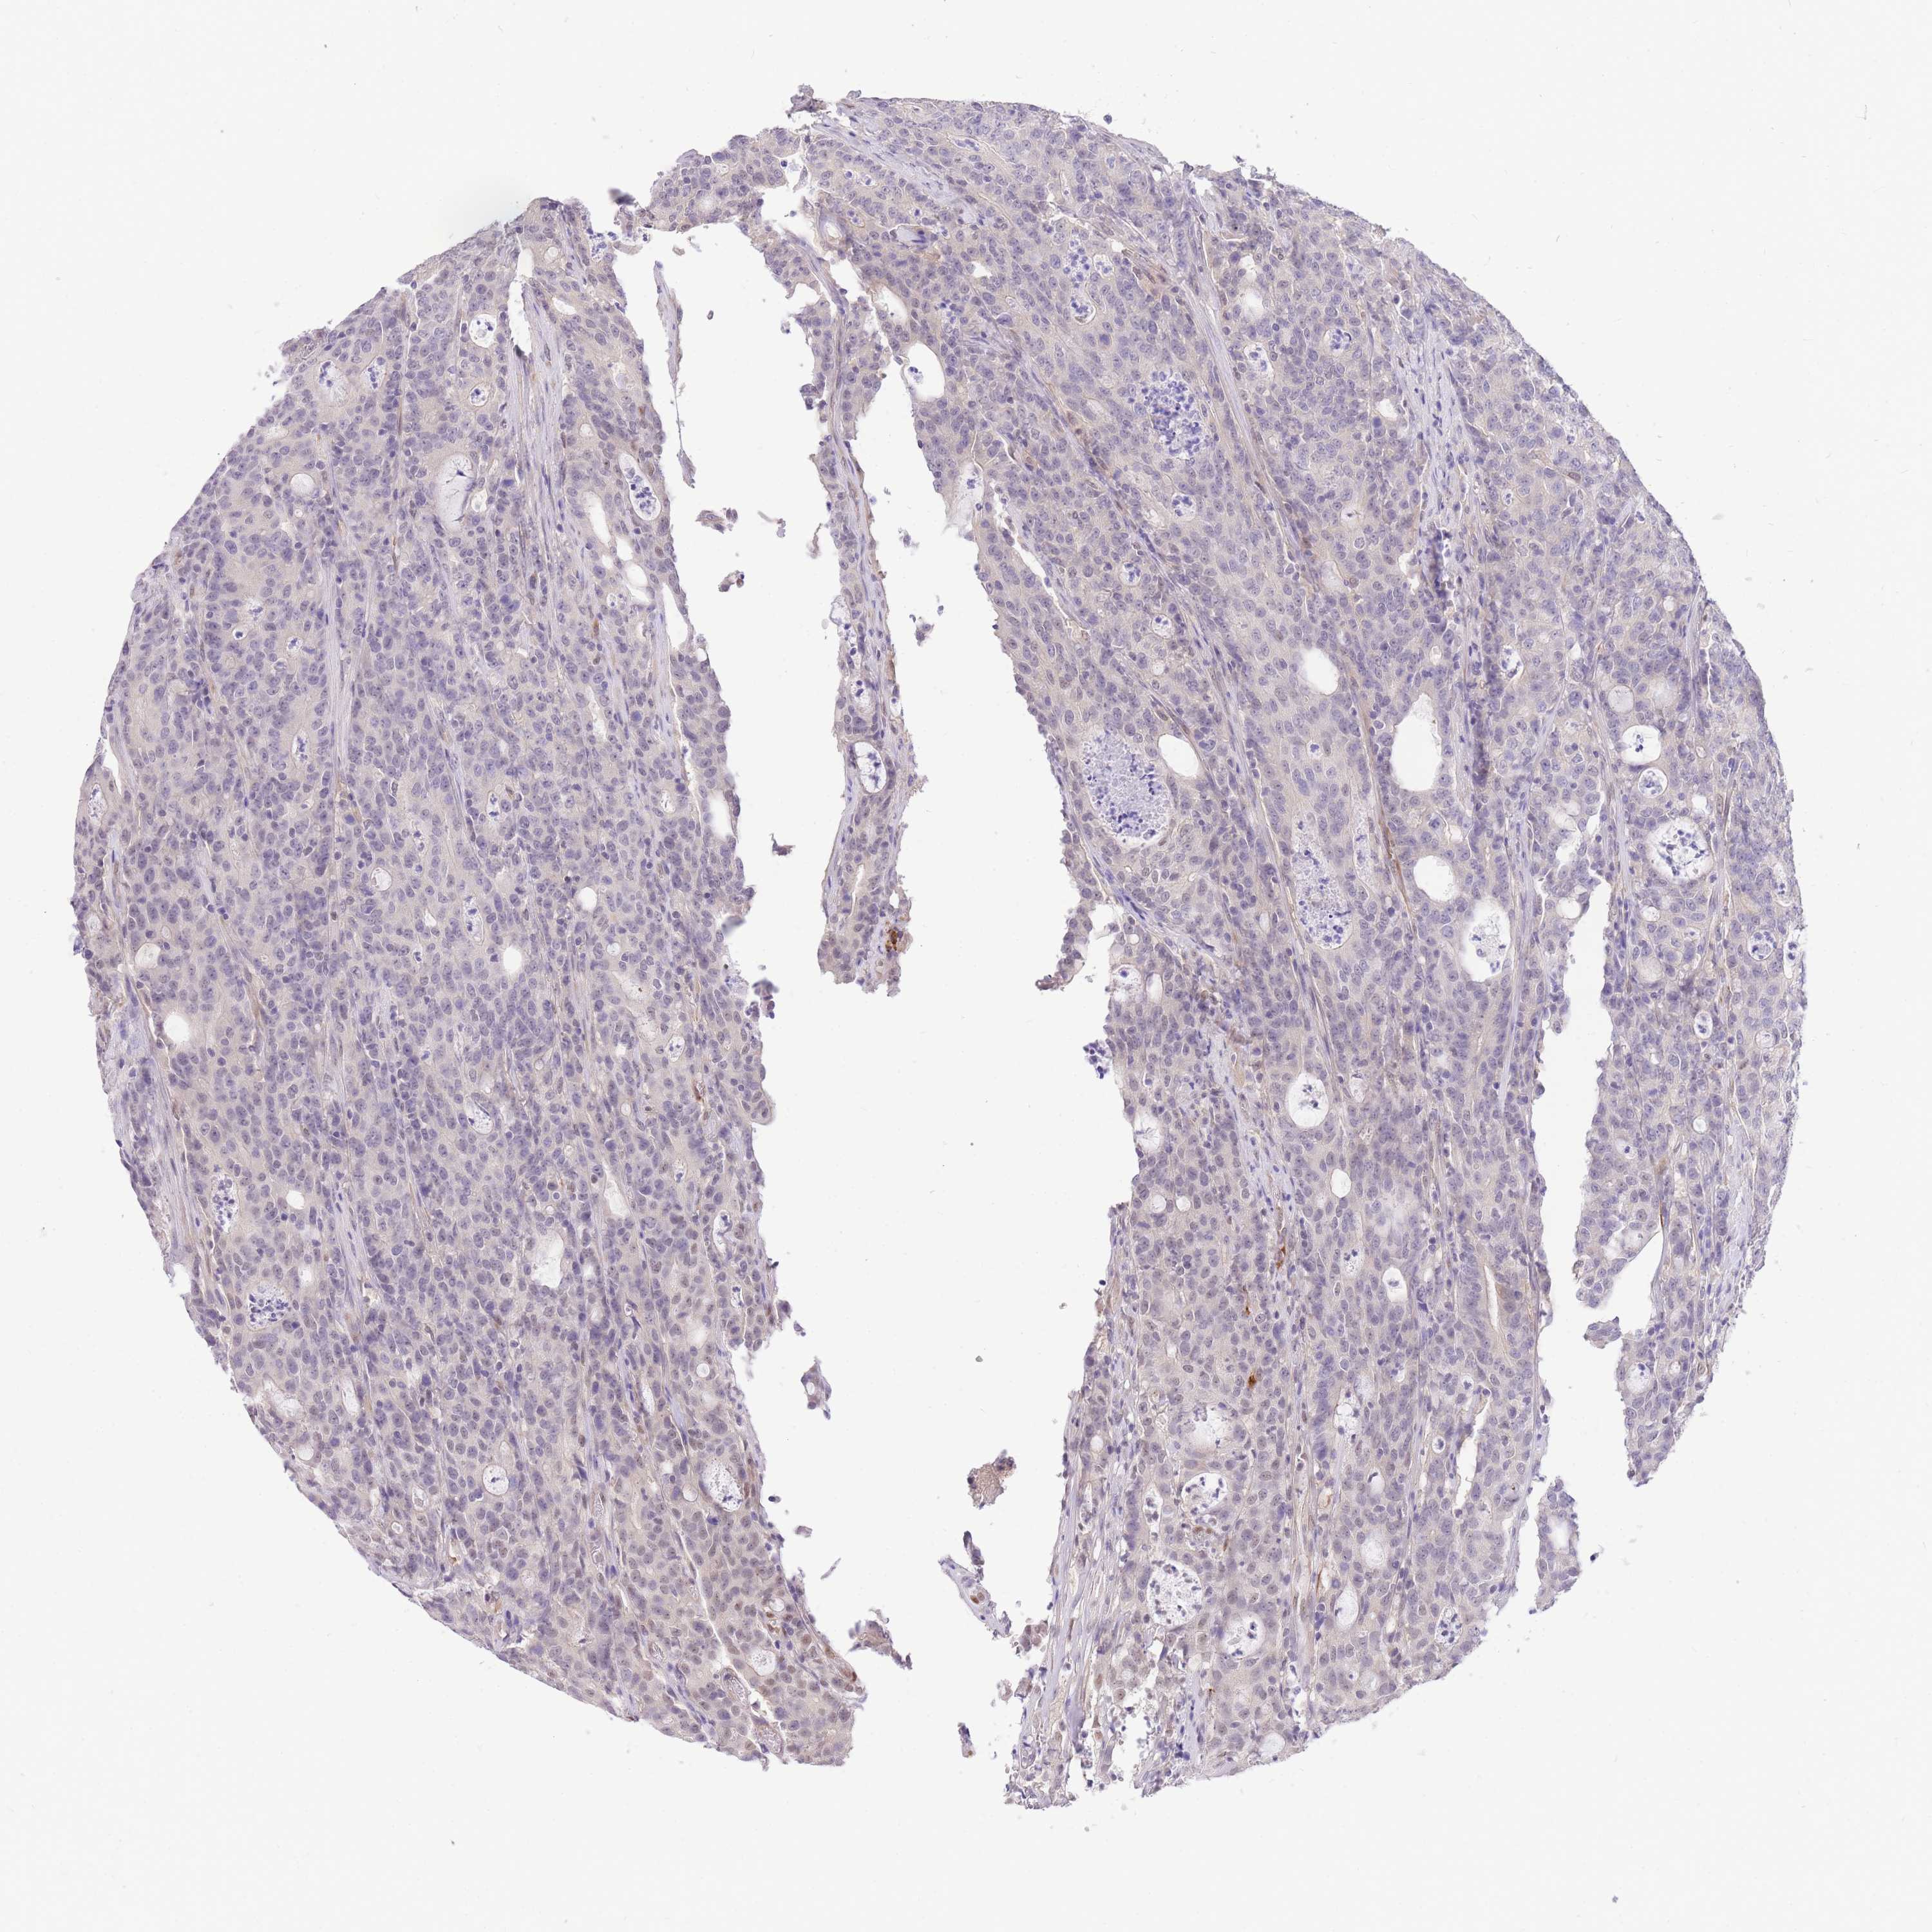

CANCER COLORECTAL CANCER Show tissue menu

Colorectal cancer

Colon adenocarcinoma